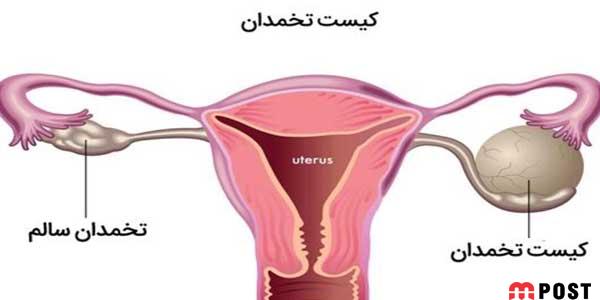

قبل از توضیح در مورد کیست هموراژیک تخمدان؟ لازم است بدانید که کیست تخمدان بیماری زنانهای است که از تشکیل یک یا چندین کیست غیرطبیعی در تخمدان سرچشمه میگیرد. کیستهای تخمدان ساکهایی حاوی مایع هستند که درون تخمدان یا روی آن رشد می کنند.

دو تخمدان شما در دو طرف رحم شما قرار دارند. هر کدام به اندازه و شکل یک بادام هستند. تخم ها که تخمک نیز نامیده میشوند، در تخمدانها رشد و بالغ میشوند و در دورههای ماهانه در طول سالهای باروری آزاد میشوند.

کیست های تخمدان کیسه ها یا کیسه های پر از مایع در داخل یا روی سطح تخمدان هستند. کیست های تخمدان خونریزی دهنده در طول تخمک گذاری زمانی که تخمک از طریق فولیکول تخمدان روی سطح آن آزاد می شود، ایجاد شده و آن فولیکول به داخل کیست خونریزی می کند. پزشکان نمی دانند چرا این اتفاق می افتد.